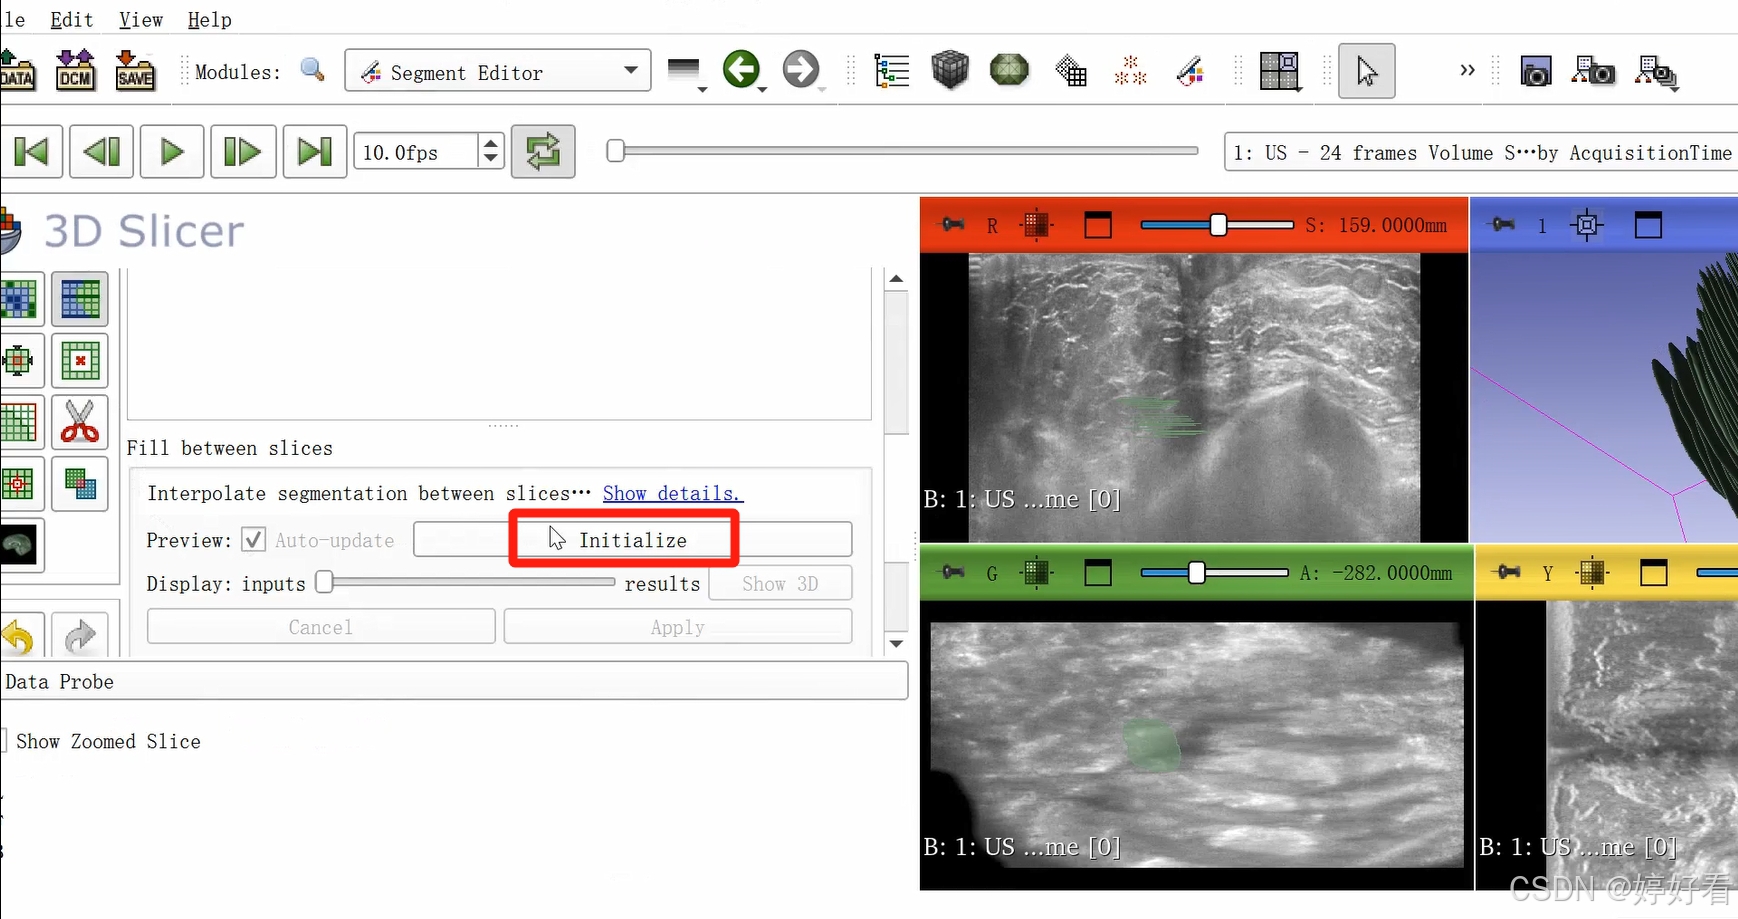

2.6 使用Fill between slices功能

上一步中完成的三维图像不是完整连续的三维图像,是一层一层的。Fill between slices这个功能可以自动填充每一层之间的间隙。选中Fill between slices,然后依次点击Initialize-Apply。